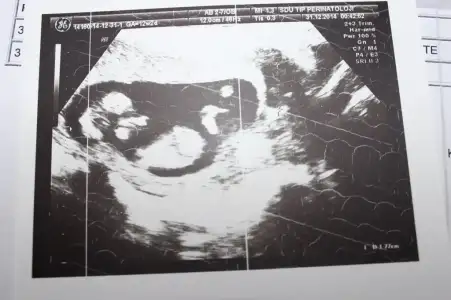

dr soylemeden siz gorun genital nub teorisi ( bebegin cinsiyeti)

IMG_1301.webp IMG_1302.webp IMG_1303.webp IMG_1306.webp

Kiz dedigim foto on haftalikmis zaten canm o haftada hepsi kiz gibi gorunur bilseydim kucuk derdim son fotodan belli erkek bebegin geliyor bence

arkadaşlar bana kız diyende var erkek diyende benim bebeğim belli etmiyomu yaa bnde anlayaadım ne paralel ne yukarı dogru :D